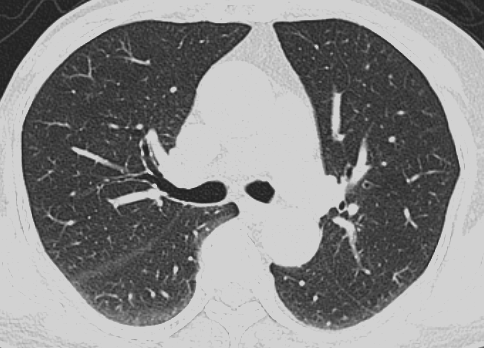

高清精准,微小病灶可见

采用先进迭代重建算法与AI智能降噪技术,在低剂量下实现高清成像,显著提升早期肿瘤、血管斑块、细微骨折等微小病灶检出率,为临床诊断提供可靠支持。

图四:百万像素 1024 * 1024 矩阵,有效提升微小病灶分辨能力